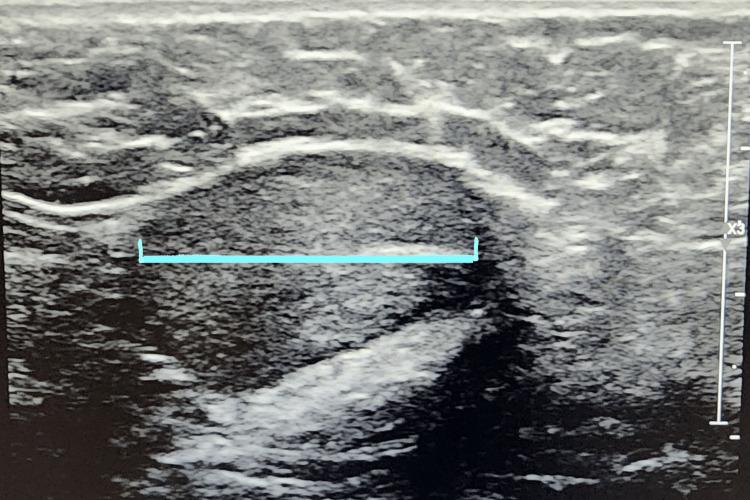

This case report presents a rare case of adult cryptorchidism, found incidentally in a 25-year-old gentleman who initially presented with abdominal and suprapubic pain and was successfully treated with staged orchidopexy. To our knowledge, to date, our case is the first published instance of bilateral cryptorchidism in an adult presenting with nonspecific suprapubic pain. Cryptorchidism is the most common genital abnormality in newborn boys, and due to its association with an increased risk of infertility and malignancy, current management involves surgical correction with orchidopexy by 12 to 18 months of life. Adult presentation of cryptorchidism is very unusual due to early intervention; therefore, bilateral cryptorchidism is even more rare. As a result, current guidelines do not address proper management for adult cryptorchidism. Therefore, after performing a thorough review of the literature on contemporary guidelines for cryptorchidism management, we aim to highlight our approach to management in this rare case of adult bilateral cryptorchidism. We suggest bilateral orchiectomy as the safest option, if the patient is amendable, or bilateral orchiopexy with long-term follow-up for testicular cancer. Although the American Urological Association guidelines recommend orchiectomy for postpubertal cryptorchid children, currently, no explicit guidelines exist for the preferred method of managing adult cryptorchidism. Due to the increased risk of infertility and testicular cancer with cryptorchidism, orchiectomy instead of orchiopexy may be the preferred surgical approach in some instances. Still, in the case of bilateral cryptorchidism, orchiectomy may not always be the most viable solution, making orchiopexy with long-term follow-up for testicular cancer the best option, such as in our case.

本病例报告呈现了一例罕见的成人隐睾症病例,该病例偶然发现于一名25岁男性,他最初表现为腹部和耻骨上区疼痛,并通过分期睾丸固定术成功治愈。据我们所知,迄今为止,我们的病例是首例已发表的成年双侧隐睾症伴非特异性耻骨上区疼痛的病例。隐睾症是新生儿男孩中最常见的生殖器异常,由于其与不孕和恶性肿瘤风险增加相关,目前的治疗方法是在12至18个月大时通过睾丸固定术进行手术矫正。由于早期干预,成人隐睾症的表现非常罕见;因此,双侧隐睾症更为罕见。结果,当前指南未涉及成人隐睾症的恰当治疗方法。因此,在对有关隐睾症治疗当代指南的文献进行全面回顾后,我们旨在强调我们对这例罕见的成年双侧隐睾症的治疗方法。我们建议,如果患者适合,双侧睾丸切除术是最安全的选择,或者进行双侧睾丸固定术并对睾丸癌进行长期随访。尽管美国泌尿外科学会指南推荐对青春期后隐睾儿童进行睾丸切除术,但目前对于成人隐睾症的首选治疗方法尚无明确指南。由于隐睾症导致不孕和睾丸癌的风险增加,在某些情况下,睾丸切除术而非睾丸固定术可能是首选的手术方法。然而,在双侧隐睾症的情况下,睾丸切除术可能并不总是最可行的解决方案,如我们的病例所示,对睾丸癌进行长期随访的睾丸固定术是最佳选择。